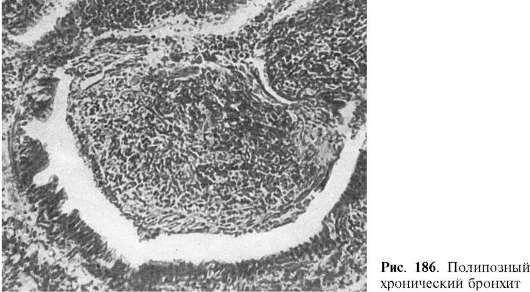

ского эпителия в многослойный плоский, увеличением числа бокаловидных клеток; в других - в стенке бронха и особенно в слизистой оболочке резко выражены клеточная воспалительная инфильтрация и разрастания грануляционной ткани, которая выбухает в просвет бронха в виде полипа - полипозный хронический бронхит (рис. 186). При созревании грануляционной и разрастании в стенке бронха соединительной ткани мышечный слой атрофируется и бронх подвергается деформации - деформирующий хронический бронхит.